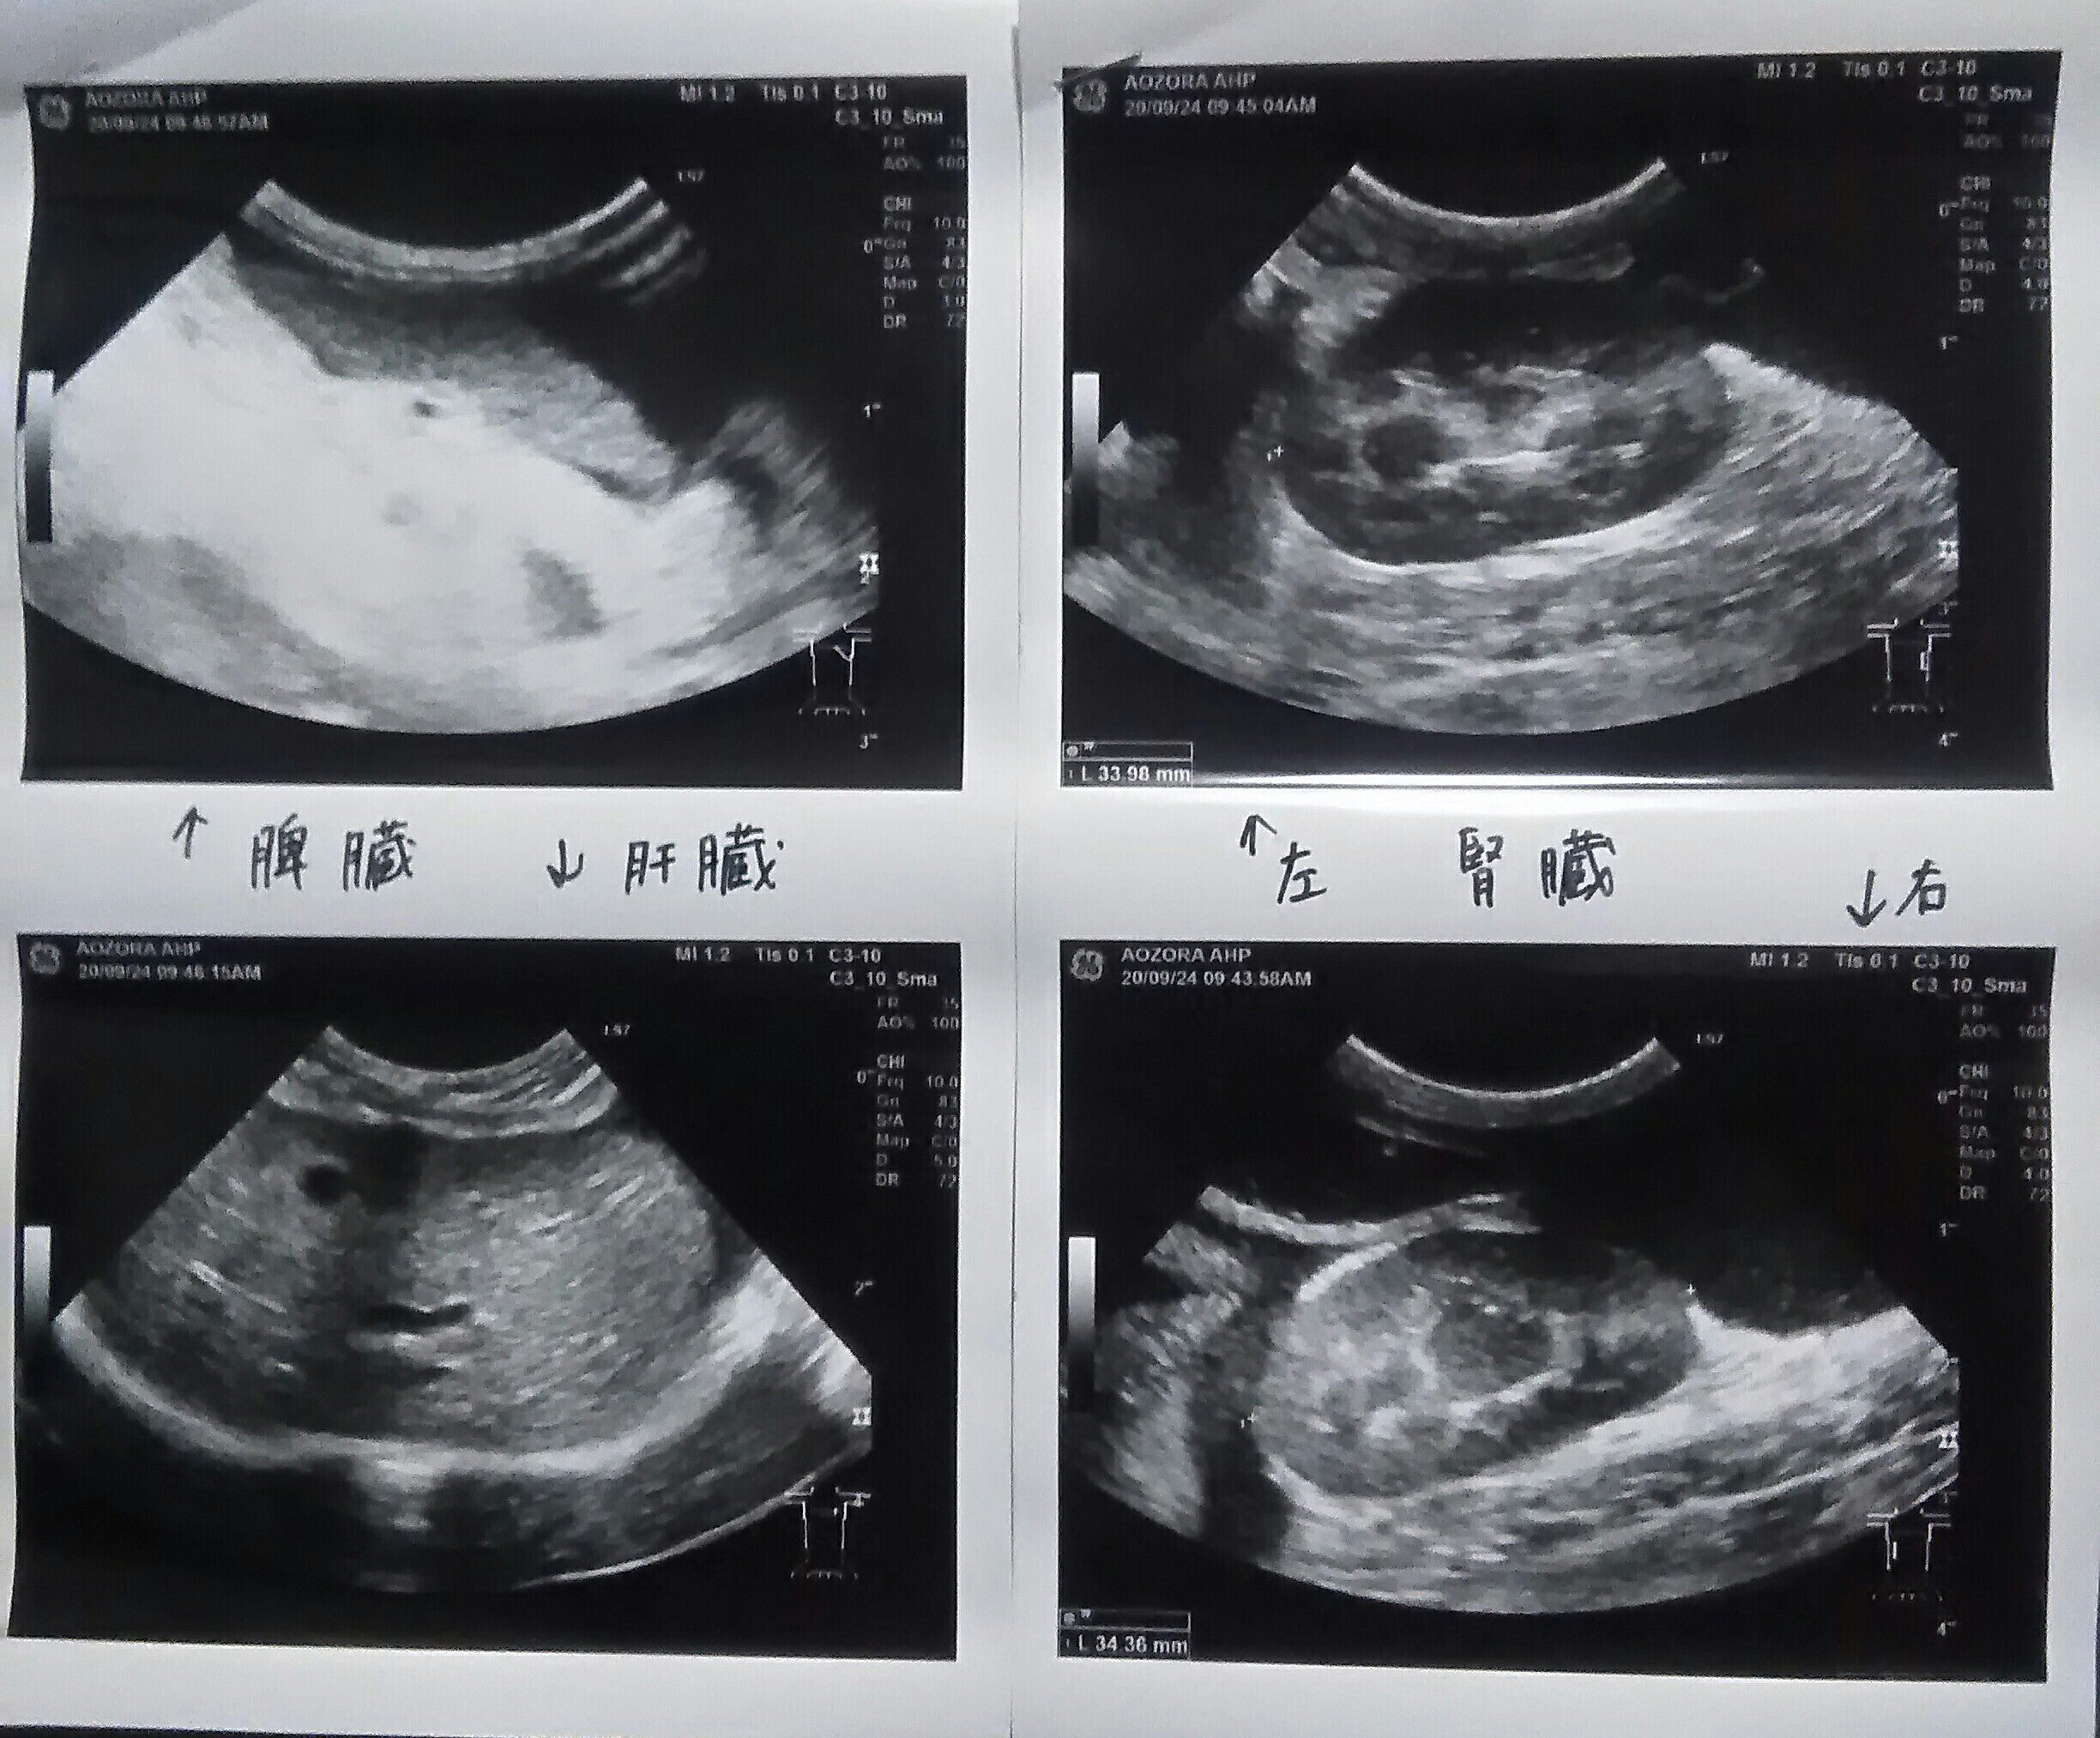

そちらの動物病院さんで、9月24日(木)に再度血液・生化学検査とエコー検査をしていただきました。

FIPであることを判断する基準は主に2つあり、1つ目は「お腹に腹水が溜まっていること」、2つ目は「A/G比の数値が1を大きく下回っていること」であると言われました。

腹水については、19日の段階ですでに溜まっていると言われ、24日のエコー検査でも、写真をいただき、やはりかなり溜まっていると説明されました。

先ほどのエコー写真の、黒い部分はほとんど腹水だそうです。(一部の黒い部分は臓器だそうです。)腹水は、放っておくと呼吸困難を引き起こす可能性があるらしいので、かなり恐ろしいです。